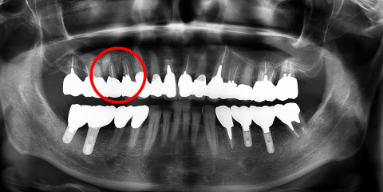

治療後

赤丸部位は骨の再生の状態を示す。

垂直的骨欠損に対して再生が確認できる